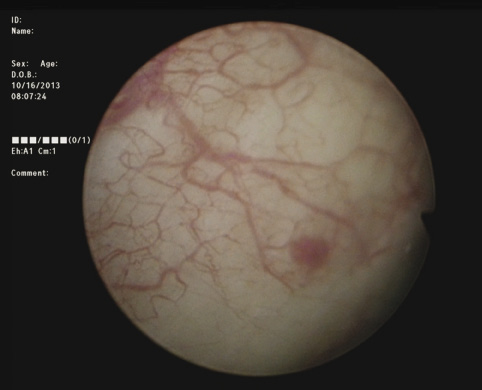

3) Complete cystoscopy is then performed in the standard fashion using WLI to re-identify the primary tumor as well as to assess for tumor multifocality, Figure 1a. This assessment is sometimes more easily done in the operating room with the patient under anesthesia. Once cystoscopy is completed with WLI, we then switch to NBI by pressing the button on the camera cord. A repeat thorough cystoscopy is then done, specifically looking for areas of hypervascularity in the mucosa, Figure 1b. These areas most likely represent occult bladder lesions. These occult lesions will be biopsied. Also, we use NBI to assess the peri-tumor vascularity to try and determine the demarcation between hyper vascular tissue and normal appearing mucosa and sub-mucosa, Figure 2. Our goal is to resect/vaporize all hypervascular tissue to a margin of normal appearing bladder mucosa and sub-mucosa.

DrCanter_Fig1a_CMYK.eps

Figure 1a. White light cystoscopy demonstrating flat bladder lesion.

DrCanter_Fig1b_CMYK.eps

Figure 1b. Cystoscopy of same lesion adjunctively using Narrow Band Imaging, highlighting tumor and surrounding vascularity.